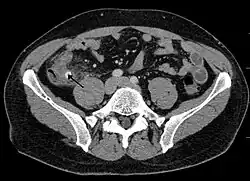

Компьютерная томография информативна при наличии спирального томографа, когда выявляется обтурация червеобразного отростка, расширение его просвета, утолщение стенки (> 1 мм) признаки свободной жидкости (воспалительного выпота) в брюшной полости.